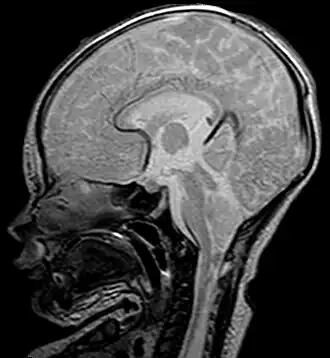

La malformación de Chiari, en honor del patólogo austríaco Hans Chiari, referida así cuando es de tipo 1 y como malformación de Arnold-Chiari reservada para la de tipo 2, es una enfermedad caracterizada por el descenso de las amígdalas cerebelosas y en ocasiones de casi la totalidad del cerebelo por el agujero occipital mayor (foramen magno), comprimiendo así el tronco encefálico; esto puede ser acompañado o no de un aumento de líquido cefalorraquídeo dentro del cráneo (hidrocefalia). Existen cinco tipos de malformación de Chiari (1, 2, 3, 4 y 0), que probablemente no se relacionan entre ellos. La mayoría de los casos pertenece al tipo 1 o 2; el resto de subtipos son muy raros de observar. Esta condición puede presentar síntomas como dolor de cabeza, vómito, dificultades al tragar, mareo, dolor en el cuello, hormigueos, caminar inestable y mala coordinación de las manos. Con menos frecuencia, las personas puede presentar síntomas como zumbido en las orejas, la debilidad, taquicardia, bradicardia, escoliosis, y apnea central del sueño.

Las malformaciones de Chiari consisten en defectos estructurales del cerebelo, órgano encargado de controlar el equilibrio y la coordinación neuromuscular. El cerebelo normal ocupa un espacio indentado en la parte inferior del hueso occipital, encima del foramen magnum, orificio por el cual desciende el extremo del tronco encefálico hacia el canal medular. La malformación de Chiari se produce cuando parte del cerebelo se encuentra ubicado por debajo del foramen.[8]

Si la apertura del espacio óseo que debería ocupar el cerebelo es menor que lo normal, el cerebelo y el tallo cerebral pueden verse empujados hacia abajo y obligados a avanzar sobre la sección superior del canal espinal. La presión resultante sobre estas estructuras nerviosas puede afectar las funciones que llevan a cabo, y entorpecer o bloquear total o parcialmente el flujo del líquido cefalorraquídeo (LCR) hacia el cerebro.[8]